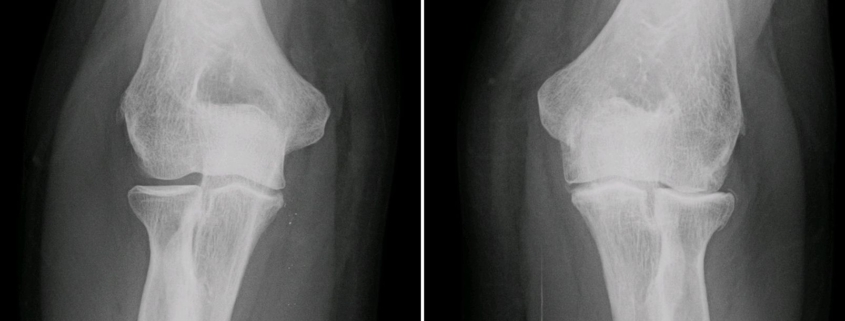

To diagnose elbow arthritis, your healthcare provider will perform a physical examination and may order imaging tests like X-rays or MRI scans to assess any damage or inflammation in the joint. Sometimes a blood test may be required to confirm rheumatoid arthritis.